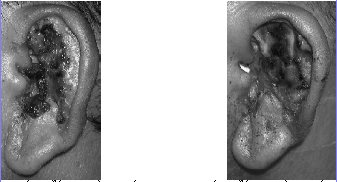

耳廓耐甲氧西林表皮葡萄球菌感染1例

耳廓耐甲氧西林表皮葡萄球菌感染1例

337x182 - 51KB - PNG